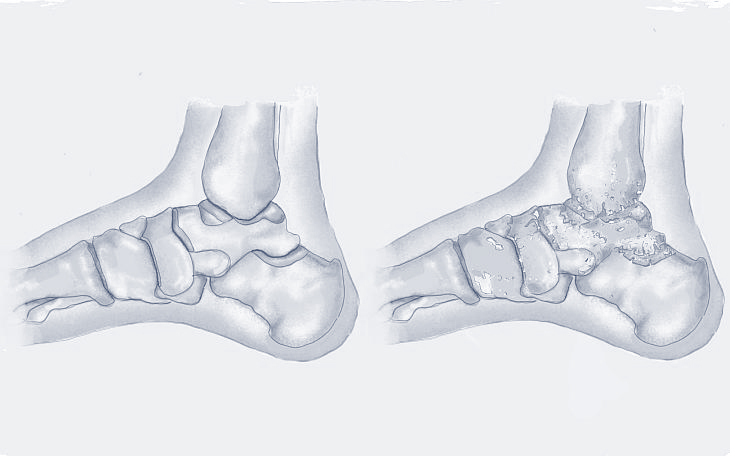

Symptome

Typisch sind Schmerzen im Sprunggelenk, die sich bei Belastung verstärken. Oft treten die Schmerzen auch morgens oder nach längeren Ruhephasen auf (Anlaufschmerz). Auch eine Schwellung, Steifigkeit und eine eingeschränkte Beweglichkeit des Gelenks können auftreten.

Ursachen

Häufige Ursachen sind Verletzungen (z.B. Knochenbrüche, Bänderrisse), Fehlstellungen des Fußes, Entzündungen oder auch eine genetische Veranlagung.

Konservative Therapie

Das Tragen von Schuhen mit guter Dämpfung und Unterstützung, Einlagen zur Entlastung des Gelenks, entzündungshemmende Medikamente, Physiotherapie zur Verbesserung der Beweglichkeit und Kräftigung der Muskulatur sowie Injektionen mit Kortikosteroiden oder Hyaluronsäure können die Beschwerden lindern.

Operative Therapie

Wenn die konservativen Maßnahmen nicht ausreichend helfen, können verschiedene operative Verfahren in Erwägung gezogen werden. Dazu gehören die Entfernung von Knochenanbauten (Osteophyten), die Knorpeltherapie (z.B. Mikrofrakturierung, Knorpelzelltransplantation), die Korrektur von Fehlstellungen oder die Versteifung des Sprunggelenks (Arthrodese). In bestimmten Fällen kann auch ein künstliches Sprunggelenk (Endoprothese) in Erwägung gezogen werden.

Bildquelle: www.docset.de